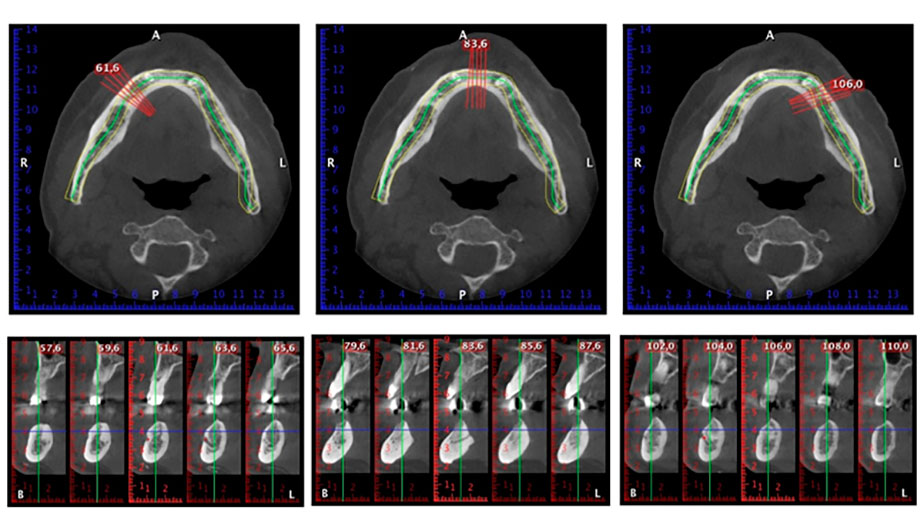

Para la planificación y la minimización del riesgo, se realizó una tomografía volumétrica tridimensional (TVD, Planmeca) que mostró que la calidad y la cantidad del tejido óseo era suficiente para la intervención quirúrgica y el tratamiento inmediato con el método Fast & Fixed. Siguiendo el protocolo de este método, se insertaron los implantes en la región de las piezas 35, 32, 42 y 45. Debido a la inclinación de hasta 45 grados de los implantes distales, el perfil de emergencia se desplazó hacia posterior y se generó un mayor polígono de soporte (fig. 3).